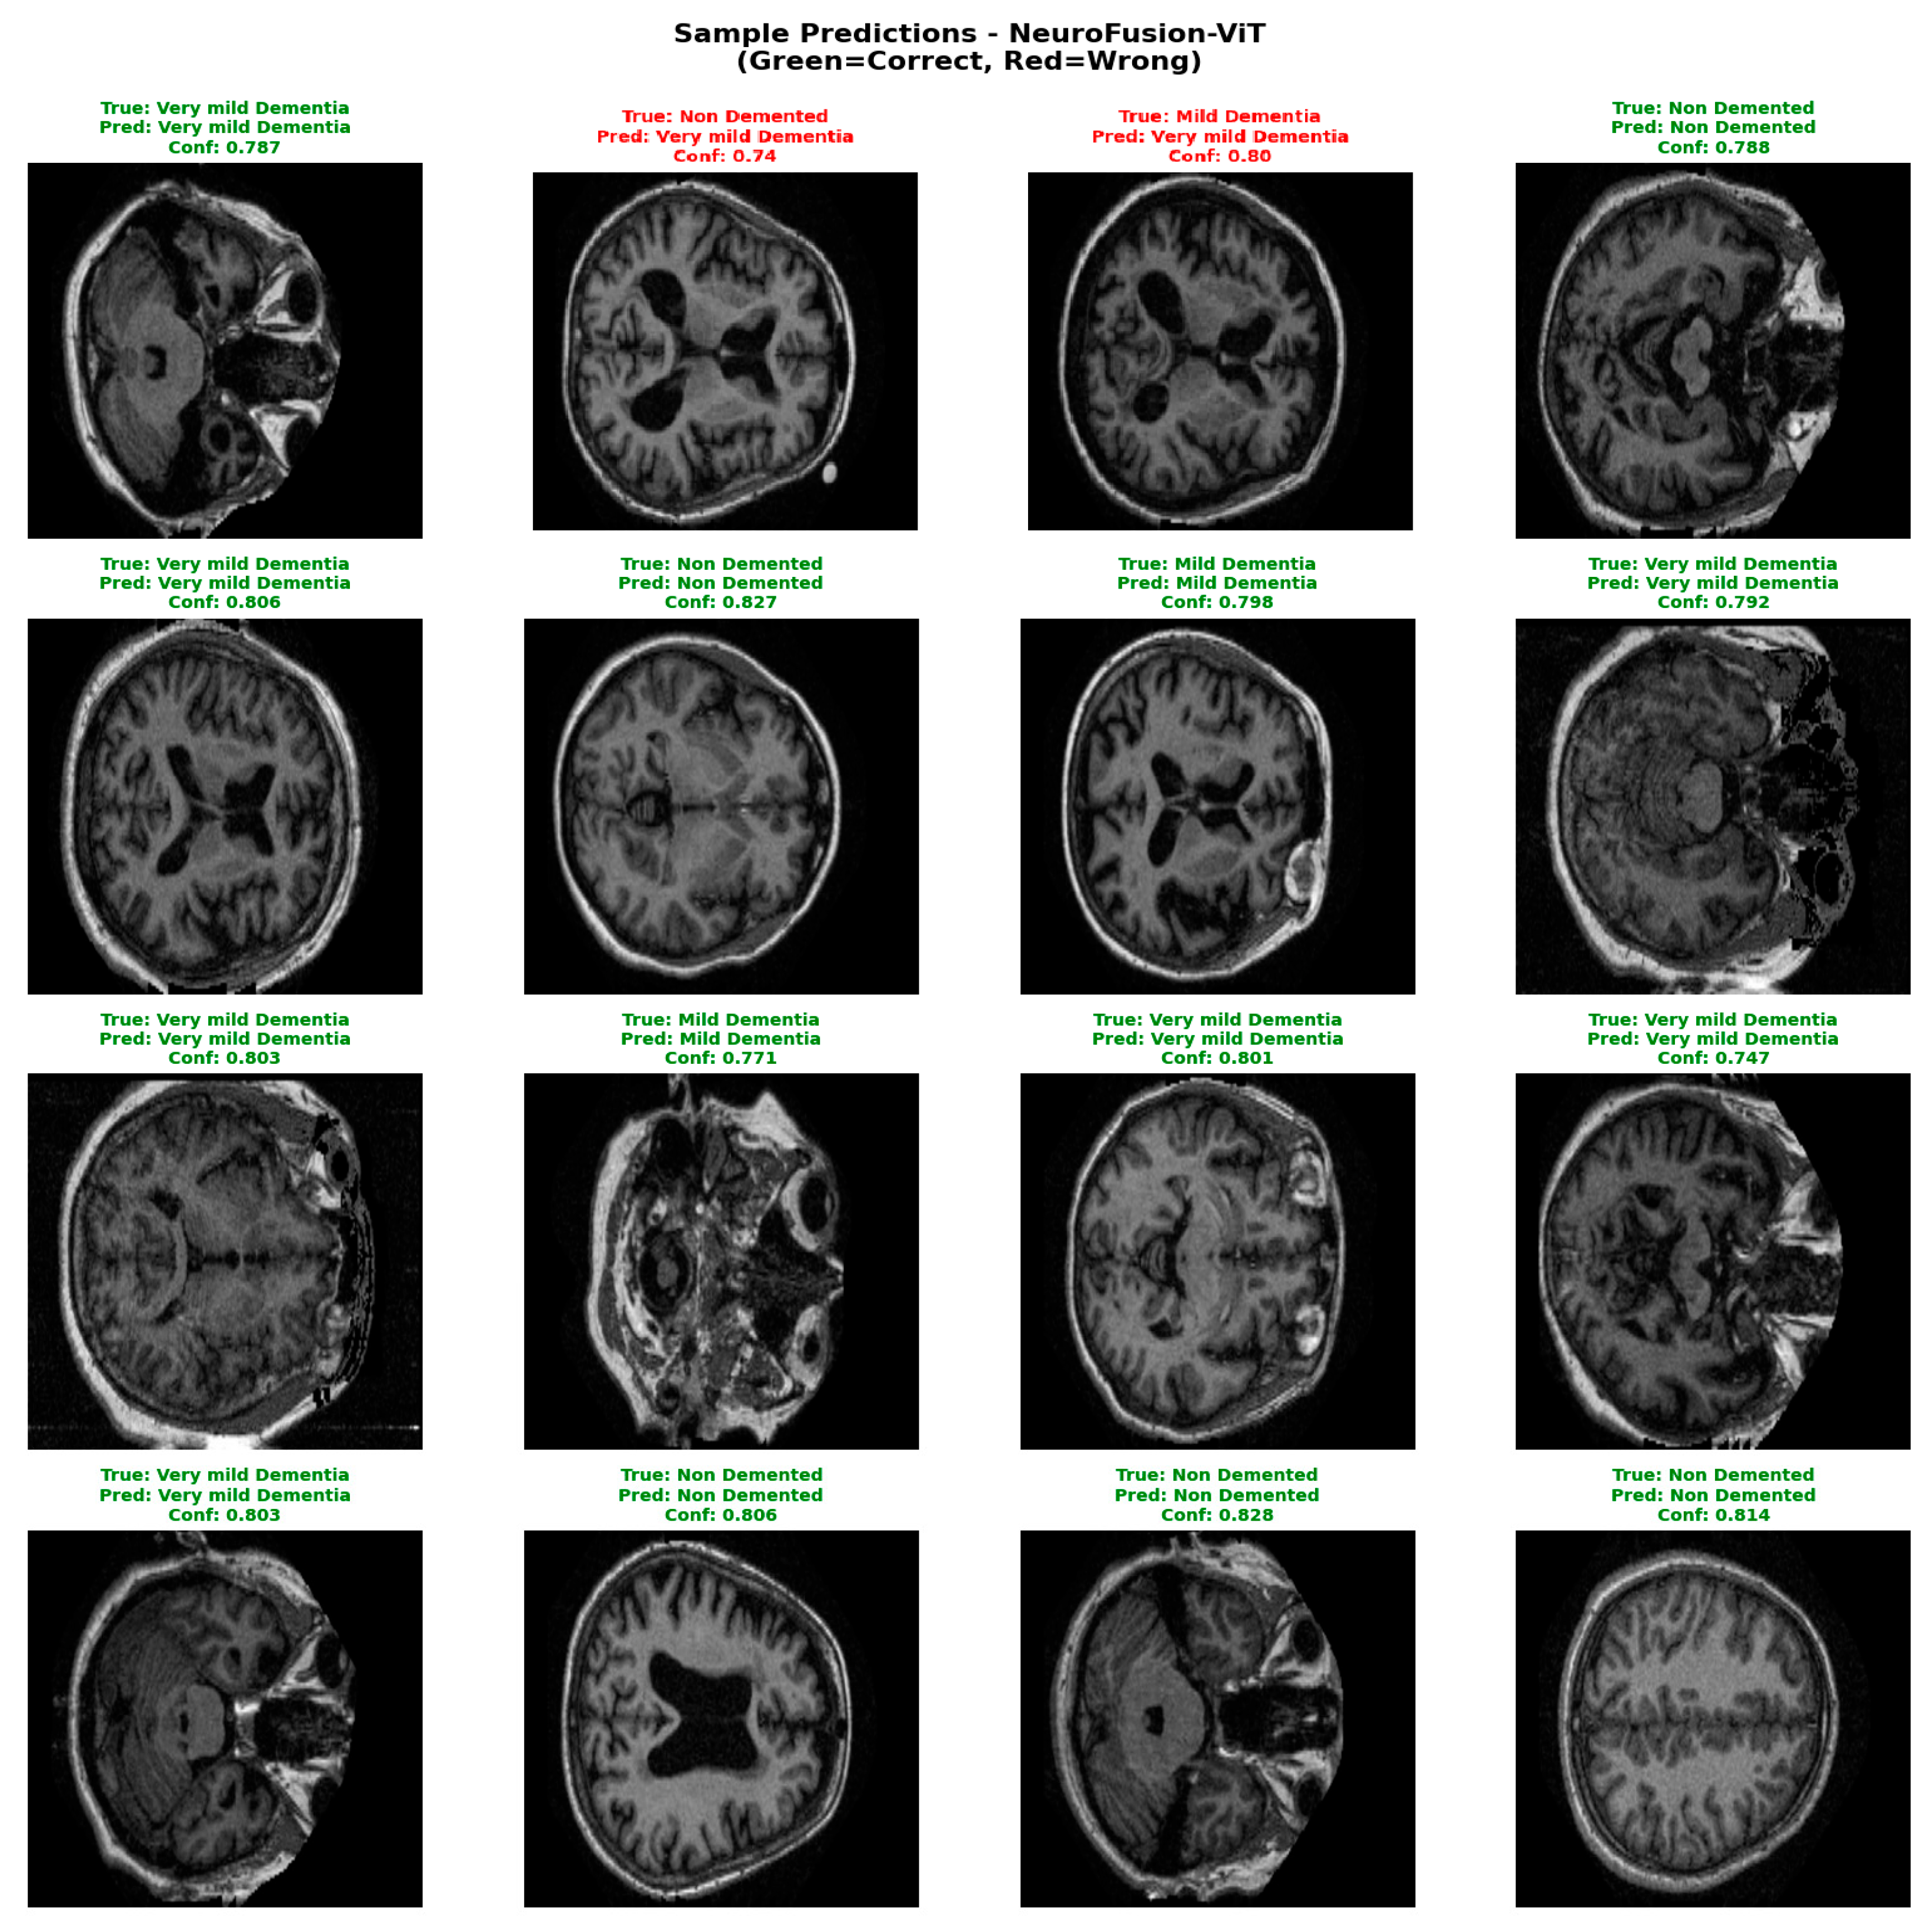

A confidence score analysis conducted to evaluate the model’s output reliability showed that the vast majority of predictions were generated with high confidence in the range of 0.75–0.82. Furthermore, the separation of correct and incorrect predictions reveals that the model can clearly distinguish ambiguous examples and that the overall decision mechanism is quite stable. Figure 8 shows the confidence distribution values for the E4 experiment.

Confidence distribution analyses have demonstrated that the NeuroFusion-ViT model produces decisions with not only high accuracy but also high reliability. The clear distinction of misclassified examples with low confidence scores confirms that the model exhibits safe error behavior for clinical use. As shown in Figure 9, the model exhibits high consistency in correctly classified examples and can clearly express the distinction between classes along with the confidence level.

Figure 9 shows the predictions of the NeuroFusion-ViT model on randomly selected MRI samples from the test set. The model correctly labeled most classes with high confidence scores and only made errors on a few low-confidence borderline cases. This supports the model’s clinically critical stable prediction behavior and strong generalization capacity. Table 3 shows the comparative training results for the E1–E4 experiments.

Figure 9. Sample predictions for the E4 experiment.